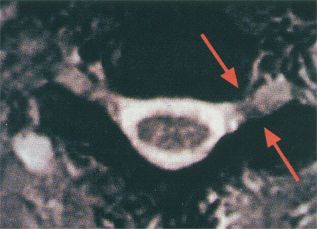

Blödningen syns på CT som subaraknoidalblödning (SAH), intracerebralt hematom (ICH) eller intraventrikulärt hematom (IVH). Ju äldre du blir desto stelare blir dina blodkärl. Risken för blödningar ökar om du till exempel faller och slår i huvudet.

Det krävs ofta ett väldigt hårt slag för att orsaka blödningar men även ett lindrigare slag kan ha förödande effekt om det träffar fel. Intracerebral blödning Etiologi - Lokalisation: i storhjärnan ( i basala ganglier, i thalamus). Män är överrepresenterade och drabbas i av fallen. Utöver detta tillkommer andra droger. Durets blödningar är blödningar i mitthjärnan och pons som tros orsakas av skador på vener och artärer som försörjer övre hjärnstammen.